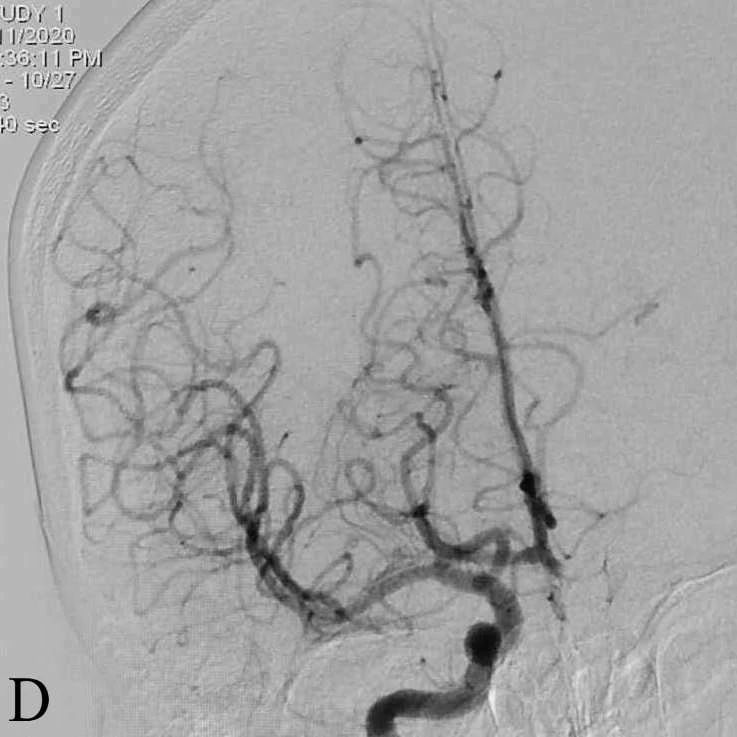

D:取栓后右侧ICA造影正位显示右侧ICA mTICI3级再通